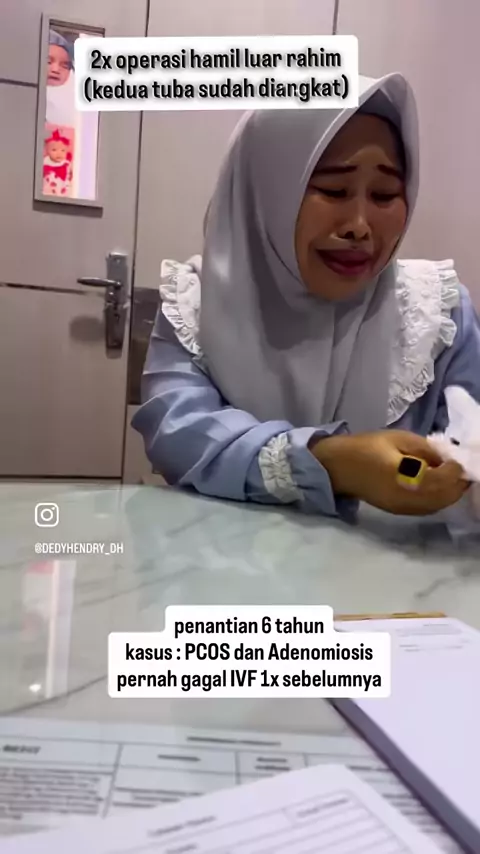

report 06/02-2026 Alhamdulillah setelah pasien ini melewati hari-hari yang berat dan panjang yaitu 2x mengalami operasi luar rahim (kedua tuba diangkat), menjalani program IVF sebelumnya dan gagal, baru datang keklinik kita @klinik_desani kemudian ditemukan adanya PCOS dan Adenomiosis, dilakukan IVF dan embrio yg didapatkan dilakukan PGTA dengan hasil keduanya perempuan (46 XX), transfer embrio beku dengan long protocol, alhamdulillah bisa hamil dan bagus jantungnya.. Alhamdulillah ya Allah @k...